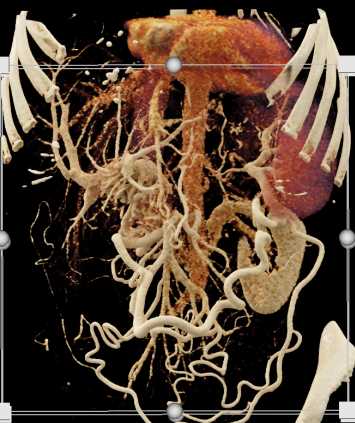

Mass Pushes on Tail of Pancreas was Ganglioneuroma